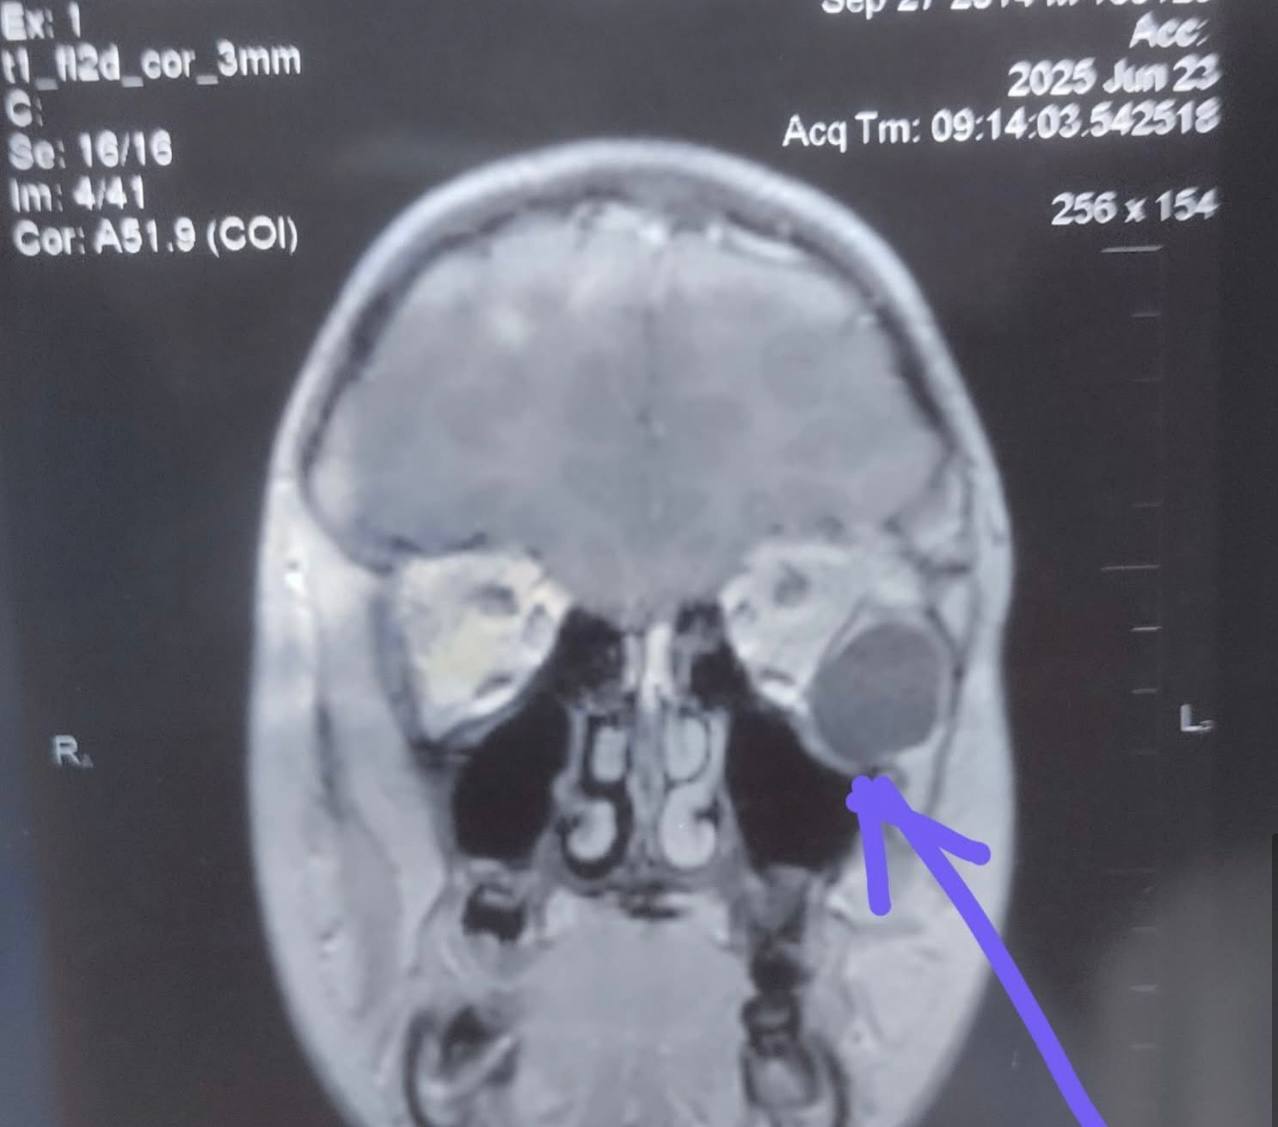

Після проведення МРТ обстеження виявили новоутвір великих розмірів (приблизно 20 мм), який зміщував очне яблуко та викликав у дитини наявні симптоми.